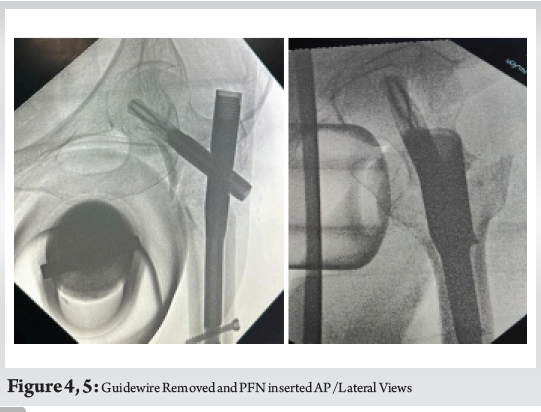

During cephalomedullary nailing, while reaming over the guide wire for the proximal lag screw, resistance was encountered followed by sudden loss of resistance. Fluoroscopic imaging revealed a broken guide wire lodged in the femoral neck (Fig. 1, 2). Attempts at removal with a pituitary rongeur were unsuccessful. (Fig. 3)